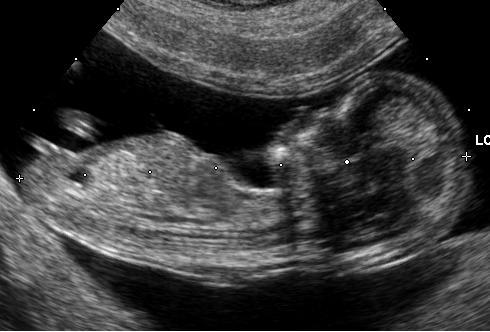

استاد باستانی پاریزی میگوید: من فکر می کردم این تشبیه جو به دختر و گندم به پسر، فقط مختص ما کرمانیها بوده است، اما اخیرا در جایی دیدم که یک پاپیروسِ مصری که شاید در ۳۵۰ سال پیش از میلاد نوشته شده باشد، برای تشخیصِ جنسیتِ جنین می گوید مقداری جو و گندم را بصورت روزانه با ادرار زنِ حامله، خیس کنند و اگر جو شروع به جوانه زدن کرد، دختر به دنیا خواهد آمد و اگر گندم زودتر جوانه زد، نوزادِ آینده پسر خواهد بود.

شاید موبدان ساسانی نیز از همین روش برای تشخیص جنین ملکه استفاده کردند و تاج را بربالای تخت وی برافراشتند تا زمانیکه شاپورذوالاکتاف متولد شد.